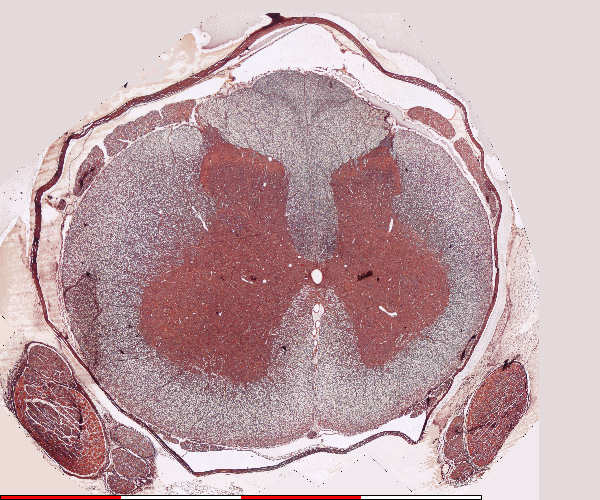

Spinal cord